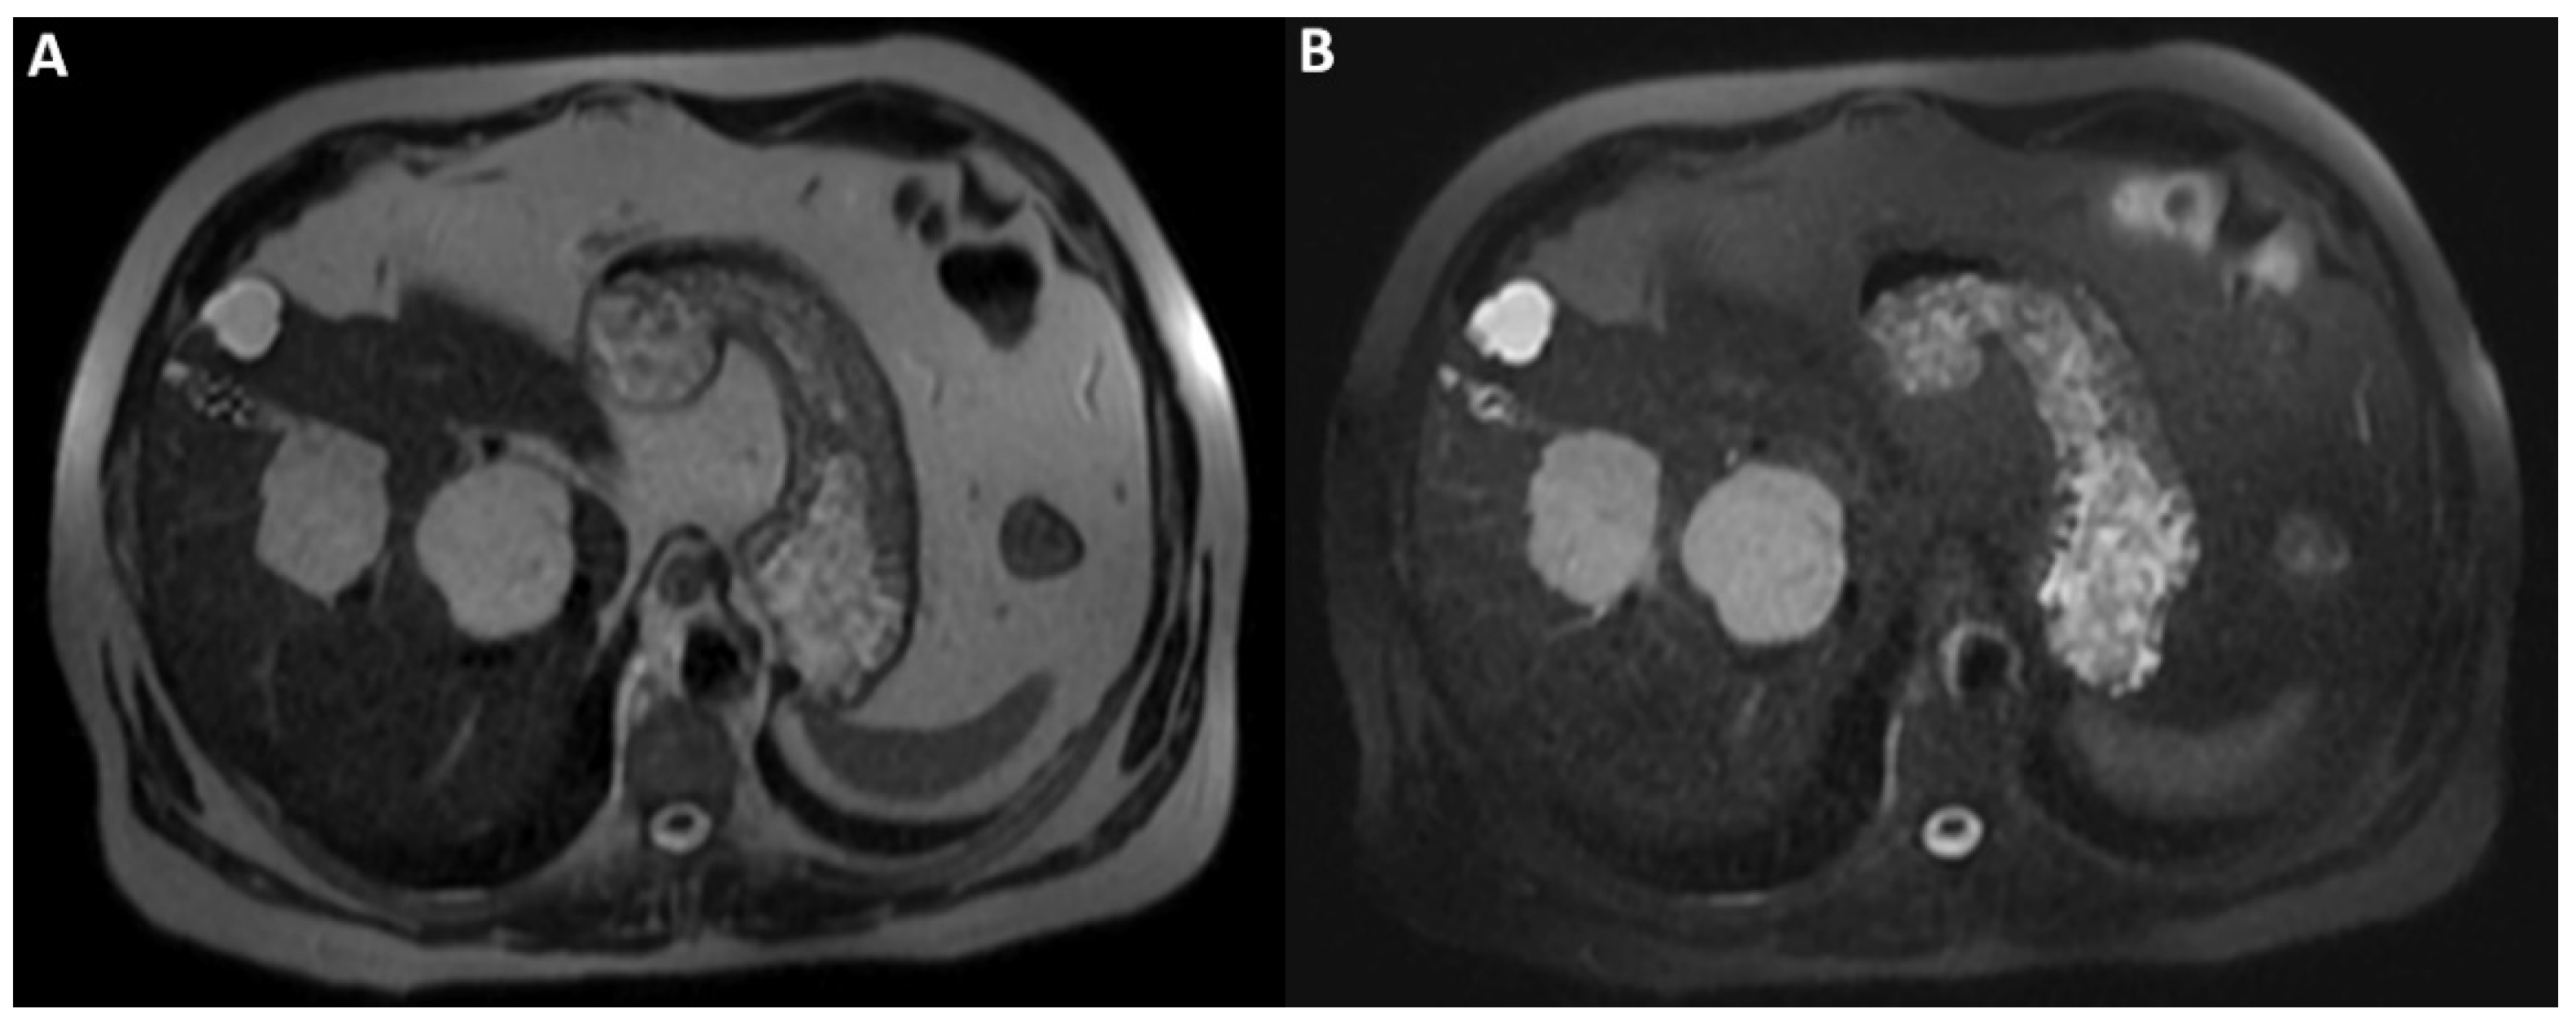

On T2WI without fat-suppression (A) and with fat-suppression (B) acquired a few days later without previous contrast agent administration; the lesions’ hyperintensity was clearly homogeneous. Therefore, the inhomogeneous signal intensity of the lesions on post-contrast T2WI is a pseudo-inhomogeneity caused by limitations of the acquisition protocol and a direct consequence of the contrast-induced reduction in the hydrogen nuclei relaxation time. Consequently, it was possible to establish the lesions’ benignity and make the final diagnosis of cavernous hemangiomas.